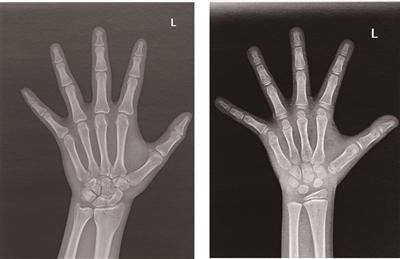

骨骺线完全闭合的20岁成年人骨龄片(左)与骨骺线未闭合的7岁儿童骨龄

教你简单识别孩子的骨龄片